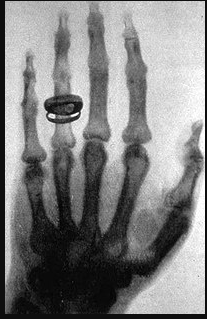

• Primera radiografia

Primera radiografia

Creada por Wilhelm Conrad Röntgen, la primera radiografía conocida la obtuvo con la ayuda de su esposa, a quien le pidió que colocara su mano izquierda sobre una placa de metal para poder “fotografiarla”.